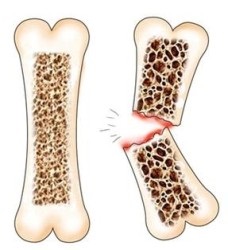

osteoporoza

Osteoporoza inseamna literalmente porozitatea osoase, scăderea densității sale. osul nostru este compus din mai multe minerale și substanțe nutritive, iar în cazul în care acestea sunt eliminate din organism, suferă întregul schelet al persoanei. În mod normal, până la 35 de ani, aceste substanțe se acumulează, consolida, face os mai dens, exercitând o mare influență asupra proceselor metabolice. Dar, după proces limită de vârstă este schimbat, iar corpul incepe sa fie epuizate, determinând o subțiere a oaselor.

oase sănătoase (stânga) și fracturi osoase cu osteoporoză (dreapta)

Osteoporoza nu este o boala rara, in special la cei care au o mulțime de fum și de multe ori bea alcool. La risc este o mulțime de femei din cauza dependentei de orice diete, alese în mod independent și fără participarea unui medic. Riscul de a dezvolta boala este mai mare pentru femei de natură și acest lucru se datorează caracteristicilor fiziologice: menstruație târziu, menopauza prematura, lactatie prelungita.

Osteoporoza pericol este faptul că boala se găsește în mod spontan. Din acest motiv, zonele afectate au timp să crească și să capteze o parte semnificativă a țesutului osos. Treptat, coloana vertebrala nu mai rezista și de a distribui în mod corespunzător sarcina, care afectează în mod inevitabil, picioarele și tocuri, așa cum este tocuri idiosincratice acționează ca arcuri.

Pentru a identifica boala cât mai devreme posibil, dar numai în cazul în care o mare atenție pentru sănătatea lor și monitorizarea periodică de către specialiști. Ar trebui să declanșeze o alarmă în cazul în care creșterea sa schimbat dramatic, a existat o îndoire a spatelui, o siguranță de rău chiar și fracturi minore.

De obicei, durerea începe să apară în spate, talie și picioare, care poate fi blamat în mod eronat pe simptomele de osteoartrita. Este important de știut că osteoporoza este rareori o fază de retur, astfel incat tratamentul sa este de a preveni apariția acesteia. Este necesar să se asigure aportul de calciu ca o „clădire“ de bază a enzimei, pentru a determina cauza bolii, în scopul de a elimina primul instigator.